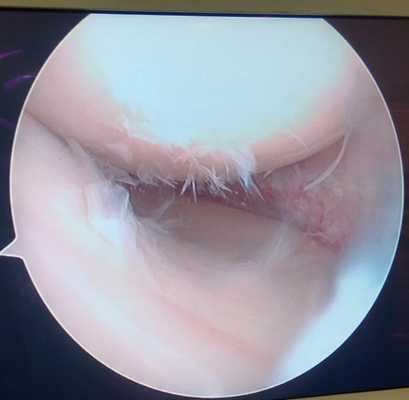

Разрыв внутреннего мениска по типу «ручки лейки» с блоком коленного сустава (невозможность полностью разогнуть коленный сустав). На фотографии хорошо виден крупный фрагмент мениска плотно зажатый между суставными поверхностями бедренной и большеберцовой кости.

Дегенеративный комбинированный разрыв тела и заднего рога внутреннего мениска коленного сустава.

Продольный разрыв заднего рога наружного мениска, сопровождающийся его гипермобильностью. При таком разрыве мениск может значительно смещаться внутрь сустава создавая ощущение механического блока, инородного тела, нестабильности в суставе, заклинивания, щелчков.